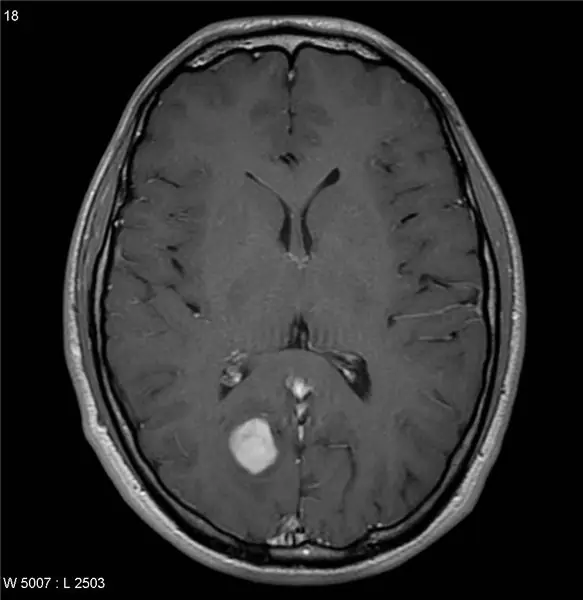

В этом руководстве вы узнаете, как использовать функции обработки изображений MatLab, чтобы сделать МРТ-сканирование мозга с опухолью и выделить изображение, чтобы показать только опухоль, а также дать некоторые анатомические подробности о ней. Перед запуском рекомендуется обновить MatLab, а также получить некоторые предварительные базовые знания в области программирования или обработки изображений.

Конечно, любой может сделать некачественный снимок с изображений Google… но вы лучше этого! Хотя иногда бывает довольно сложно найти такие виды сканирования, важно убедиться, что вы используете правильные изображения без каких-либо водяных знаков или дополнительного шума из-за плохой обработки изображений со сторонних веб-сайтов. Есть много онлайн-баз данных, которые публикуют изображения для исследовательских целей, которые вы можете использовать. Некоторые базы данных включают Aylward и OpenfMRI. Вот ссылка для начала: https://www.aylward.org/notes/open-access-medical-…. Четкое и точное изображение МРТ - это первый шаг к тому, чтобы стать профессионалом в области обработки изображений.